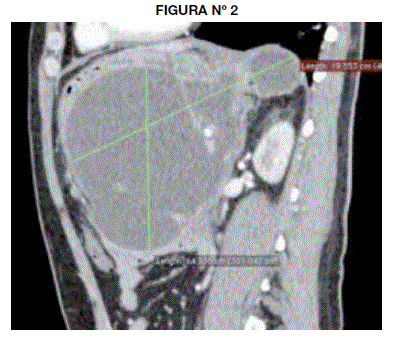

En la tomografía se observa una colección líquida multilobulada de aspecto homogéneo (10.8 UH) y baja densidad, de 2795cc de volumen calculado (19.18 X 19.55 X14.33cm) localizada en el saco menor (entre la pared posterior del cuerpo gástrico y el páncreas) y con extensiones a los espacios gastro-esplénico y subfrénico izquierdo contactando la fascia pararrenal anterior. Tiene paredes definidas con espesor máximo de 4.8mm.(Fig 1, Fig 2).